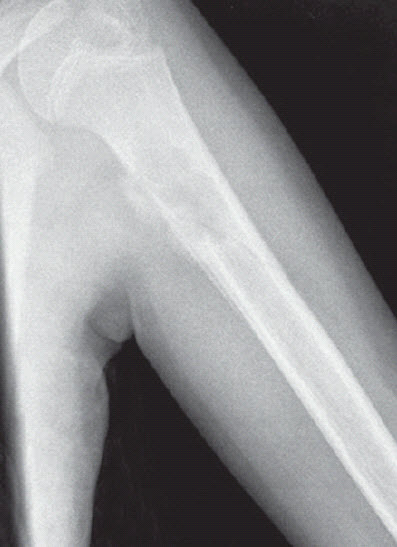

Anteroposterior and lateral views of the patient’s left humerus were ordered.

What do these radiographs show?

The radiographs show a centrally placed lytic lesion with lobulated contours and a well-defined transition zone in the proximal shaft of the humerus. An oblique pathological fracture runs through the cyst No other lesions are visible. A thick periosteal reaction on the medial aspect of the lytic lesion is also present; the peri osteal reaction is atypical in this case; however, the radiographs were obtained 10 days after the fall.

This is a unicameral, or simple, bone cyst. Many of the lesions in the differential diagnosis, including aneurysmal bone cyst, osteomyelitis, malignant lytic lesion (such as eosinophilic granuloma or bone metastasis), can be excluded on the basis of location. The location of simple bone cysts is usually the humeral head, ball of the foot, proximal femur, or proximal humerus or calcaneus.

A simple bone cyst may be an incidental finding. However, like this child, most patients present with a pathological fracture. The pathognomonic sign after a fracture is a fallen fragment in the most dependent portion of the cyst. Occasionally, a periosteal reaction can be seen. A simple bone cyst is a fluid-filled cavity lined with fibrous tissue. It is thought to result from venous outflow obstruction, which leads to an increased intraosseous pressure and a consequent stimulation of osteoclastic activity. This benign lesion usually develops within the first 2 decades of life. The cyst causes bone instability and sometimes may be associated with pathological fractures after relatively minor trauma.